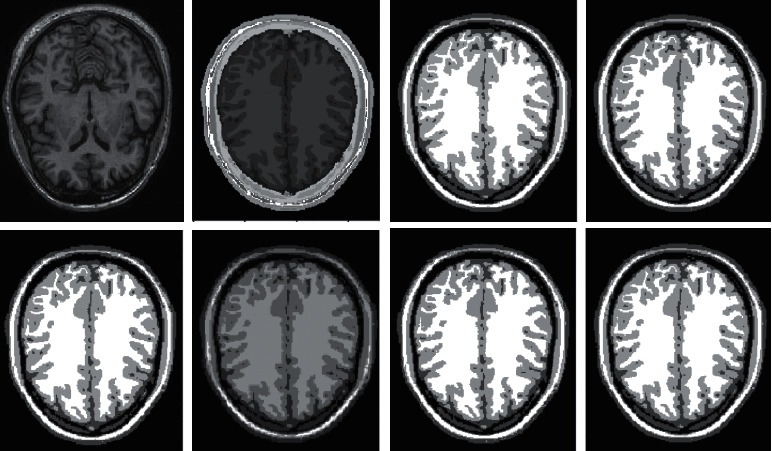

Imaging of the human brain makes extensive use of magnetic resonance imaging (MRI), which, as we all know, offers several benefits, including strong contrast in soft tissues, the absence of radiation damage, and widespread use. The segmentation of brain tissue by MRI not only contributes to the study of the function and anatomical structure of the brain, but it also offers a theoretical foundation for the diagnosis and treatment of brain illnesses [25]. Because of this, the achievement of correct tissue segmentation with MRI has a very significant impact on clinical diagnosis and therapy. Gray matter (GM), white matter (WM), cerebrospinal fluid (CSF), muscle, bones, and other important brain structures can be seen in clinical MRI brain images, as depicted in Figure 1. However, due to the fact that the human brain is highly complicated in its structure and that there are many different types of brain tissues, the human brain structure of each individual has its own set of distinctive qualities. Because of these several circumstances, the process of segmenting brain tissue will be challenging. As a result, the development of an outstanding segmentation algorithm that is appropriate for every MRI brain tissue is a topic that presents a significant amount of difficulty. While doing so, it also encourages the research of brain tissue segmentation algorithms and has become a center of attention for research at the present time. In clinical practice, it is frequently required to present a three-dimensional model of the structure of brain tissue in order to offer a foundation for the diagnosis and treatment of a patient. For instance, if brain surgery is required, the procedure can be planned and simulated in accordance with the three-dimensional anatomy of the brain. This makes it easy for the focus to rapidly and properly determine the place of the surgery [26–28]. In addition, the goal of visualizing brain tissue is to finish the job of segmenting it, which is the concept of visualization. As a result, the process of segmenting brain tissue has significant use in the field of medical diagnosis.

Figure 1.

Tissue segmentation of human brain. (a) Raw image; (b) segmentation result; (c) white matter; (d) gray matter; (e) CSF.

Ten brain MRI samples are chosen at random from the BrainWeb database in order to test the full segmentation performance of various clustering techniques. Because of the confines of the available area, we will only be analyzing a select few examples of typical image segmentation findings. For the MRI brain tissue to preserve its precise information, the clustering technique is required. This is due to the complicated structure of the tissue. Therefore, in order to conduct a comparative analysis of various algorithms, the research applies the clustering algorithms that were selected to the segmentation of MRI brain tissue. The results of the segmentation performed by the various algorithms are displayed in Figures 4 and 5.

Figure 4.

Comparison of clustering results of different algorithms for Figure 1.

In human brain magnetic resonance scans, there are many structural tissues that do not belong to the brain, such as fat, the skull, muscle, and other tissues. Because the gray information of these tissues and the gray information of particular brain structures are so highly comparable to one another, proper segmentation of brain tissues is made more difficult as a result. Therefore, when segmenting brain tissue, it is required to exclude the tissues that do not belong to the brain in order to assure the correctness of the segmentation. This is done to ensure the correctness of the segmentation. Nevertheless, the procedure of removing tissue that is not part of the brain is challenging and complicated. In this study, the nonbrain tissues have been grouped together under the same category or cluster. Figures 4 and 5 show the segmentation results, which show that the segmentation results of the K-means clustering algorithm have a lot of noise, the segmentation results of the FCM algorithm contain a small amount of noise in white matter and cerebrospinal fluid, and the segmentation results of the hierarchical cluster algorithm remove the noise, but the cerebrospinal fluid in the brain sulcus is also smoothed out. These results can be seen by looking at the segmentation. On the other hand, the results of the mean-shift algorithm's segmentation are the most accurate of all of them. Despite the fact that Figures 4 and 5 demonstrate the results of segmentation using different methods, they are unable to portray the results of distinct tissues in a way that is intuitive. As a result, the experiment provides evidence of the segmentation outcomes of several categories. The benchmark of several different types of tissues in the selected image is shown in the first row of Figures 6–11. The remaining rows of the figure contain the clustering results corresponding to K-means clustering, fuzzy c-means clustering, maximum entropy clustering, Gaussian mixture model, mean-shift, and hierarchical cluster, making it easy to compare the clustering results produced by various algorithms. The K-means clustering technique is discovered to have flaws when they are compared to other algorithms, and the results of the clustering are found to be largely one-sided, meaning that they can only segment a portion of the region.